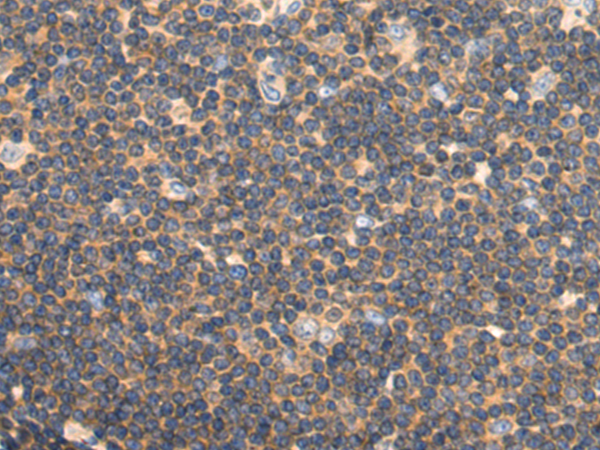

分类: 科研抗体货号: P13788别名: CAM2; CAMK2; CAMKB; MRD54; CaMKIIbeta应用: WB,IHC反应种属: Human